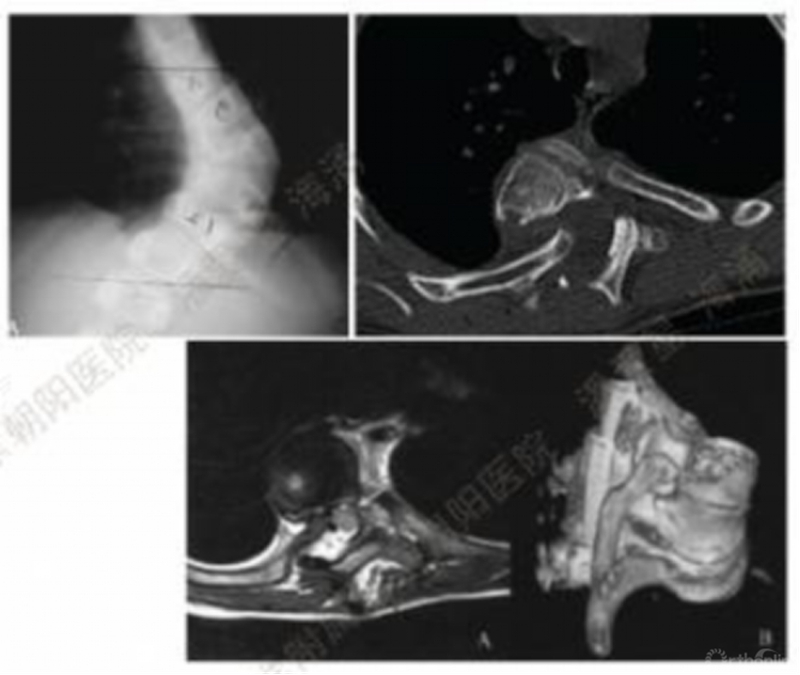

1型脊髓:髓外观形态呈光滑的圆形或椭圆形,在脊髓和顶端凹椎弓根和/或椎体之间可见脑脊液(CSF);

2型脊髓:脊髓外观形态呈光滑的圆形或椭圆形,在脊髓和顶端凹椎弓根和/或椎体之间未见脑脊液(CSF);

3型脊髓:脊髓外观形态在顶椎凹椎弓根处受压变形/变平,在脊髓和顶端凹椎弓根和/或椎体之间未见脑脊液(CSF)。

文章共纳入了128例胸段脊柱畸形患者,105例患者(82%)接受了后路截骨矫形手术,其中23人(18%)接受了VCR截骨。1型81例(63%),异常监测6例(7%);2型32例(25%),异常监测4例(12.5%);3型15例(11.7%),异常监测12例(80%)。3型脊髓患者的平均年龄较年轻,且畸形程度及畸形角度比例较1型及2型相比明显更为严重

在回归分析中的结果:

1型脊髓是脊髓电生理监测信号异常事件的保护因素(OR=0.17,P=0.0003)。2型脊髓与电生理监测信号异常的发生件没有关联(OR=0.66,P=0.49)。3型脊髓是脊髓电生理监测信号异常事件的危险因素(OR=28.3,P<0.0001)。

评估矫形术中发生神经监测异常事件风险的一种有效的分类模型。可用于指导手术医师指定手术计划及进行术前患者沟通。3型脊髓在畸形矫正过程中监测数据丢失的可能性相对较高,术前做好进行顶椎凹椎弓根切除术或VCR的准备。出现神经监测异常时避免过度地矫形。